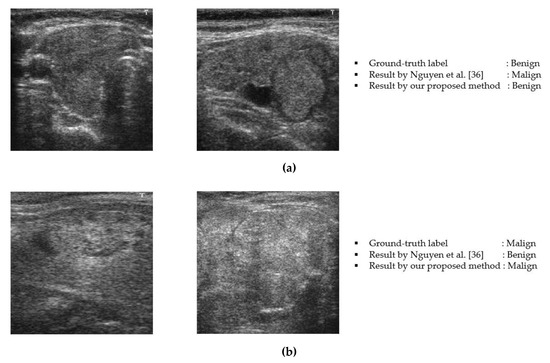

3.5. Performance Comparisons of Proposed Method with the State-of-the Art Methods

3.6. Analysis and Discussion